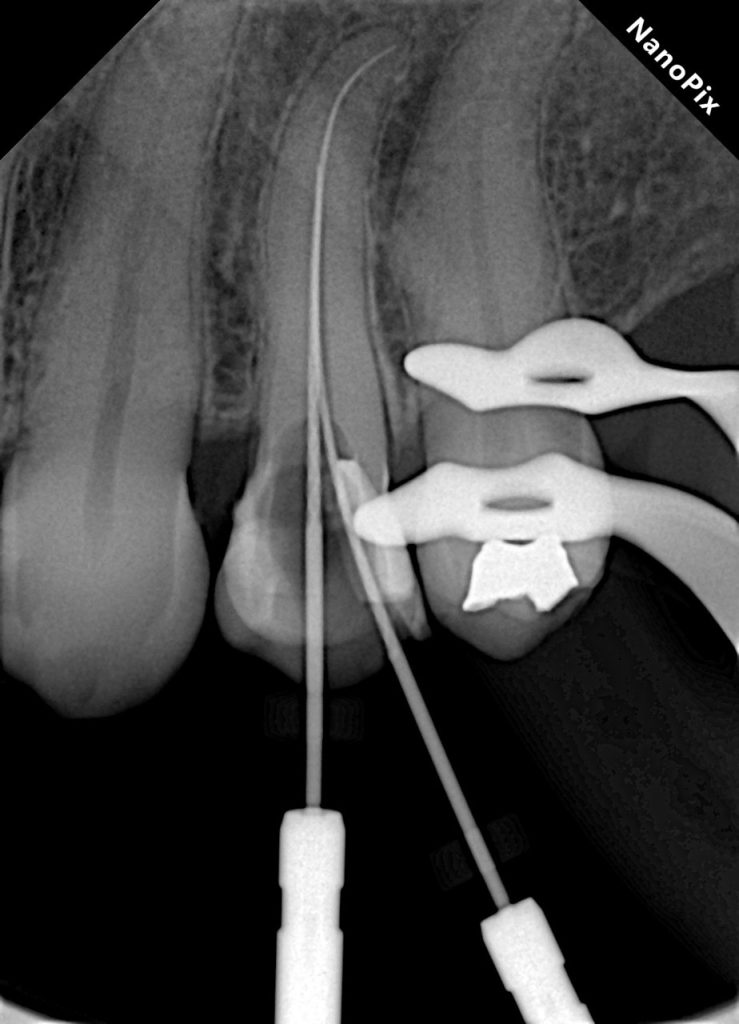

This case demonstrates the complete management of a maxillary premolar with irreversible pulpitis and compromised coronal structure. The treatment involved root canal therapy under rubber dam isolation, followed by adhesive restoration to ensure functional and esthetic rehabilitation.

4. Cleaning & Shaping

5. Obturation